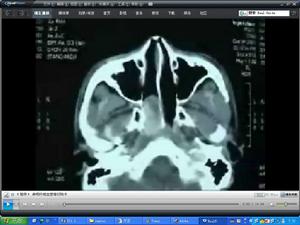

影像學檢查努力 CT和MRI福氣檢查可清晰顯示瘤體位置大小形態了解腫瘤累及範圍和周圍解剖結構的關係大把數字減影血管造影(DSA)可了解腫瘤的血供並可進行血管栓塞以減少術中出血。

根據症狀及檢查結果、性別、年齡,對典型病人多能診斷。由於此瘤極易出血,一般不做活檢X線片及CT對腫瘤大小、擴展方向和範圍,有一定診斷價值。國外學者根據CT待檢查提出放射影象學分期:Ⅰ期,腫瘤位於鼻咽部、後鼻孔及蝶竇;Ⅱ期腫瘤向前突入鼻腔、篩竇上頜竇頰及眶內側或向外擴展入翼上頜窩;Ⅲ期,腫瘤向外擴展入顳下窩及顳窩、頰、眶外側;Ⅳ期,腫瘤向顱內擴展。鼻咽血管纖維瘤具有特徵性臨床表現,但須與鼻咽部惡性腫瘤、纖維性鼻息肉和後鼻孔息肉相鑑別。惡性腫瘤息咽表現與鼻咽血管纖維瘤不同,腫瘤發展快有早期頸淋巴結轉移活檢可確診。鼻息肉質較軟,不易出血,觸診易活動,多有蒂發源於鼻腔或鼻竇。